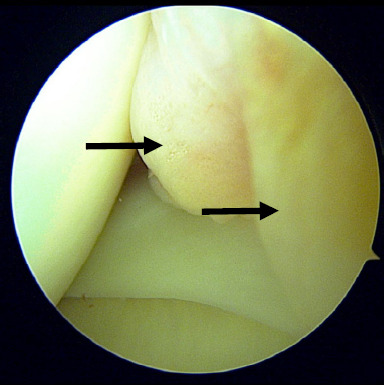

This report presents the case of an 18-year-old female student with a low BMI, who was otherwise healthy. She presented with chronic anterior right knee pain persisting for 1 year. The pain began spontaneously and gradually increased in severity, especially during long distance walking and standing for more than 15 minutes. The symptoms did not subside with medication and physiotherapy. All biochemical and radiological investigations to rule out other related possible aetiologies were unremarkable. The patient eventually underwent an arthroscopic knee surgery, during which the intraoperative findings revealed the Hoffa fat pad over the anteromedial knee joint. This was debrided and after surgery, she was symptom free and had resumed her normal activities.

Abstract Image